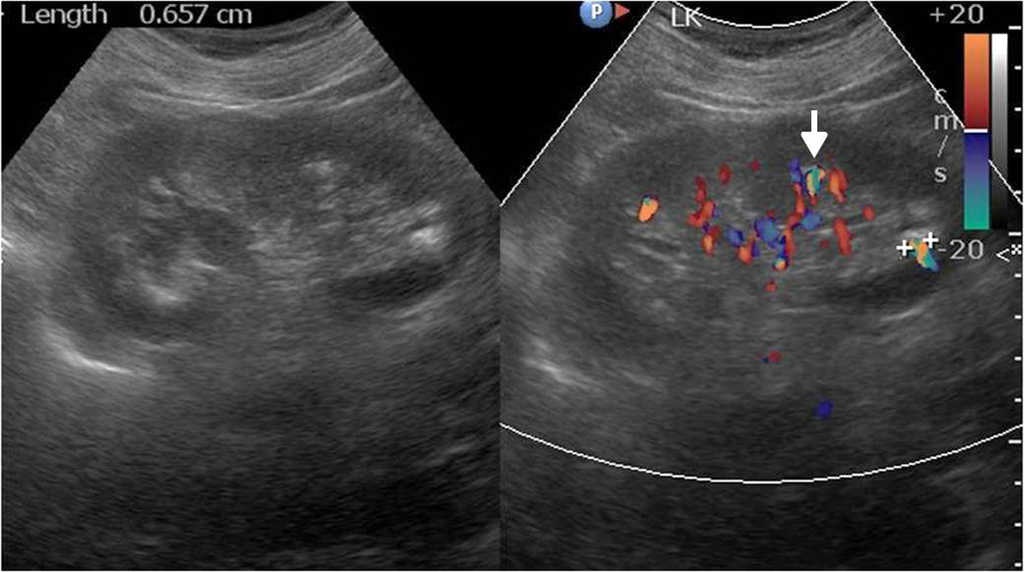

Los c??lculos se visualizan f??cilmente con el ultrasonido cuando generan sombra ac??stica posterior, pero a veces por su tama??o peque??o o el tejido circundante se dificulta su reconocimiento. En estos casos, el artefacto de centelleo en el Doppler color, consistente en la alternancia de color por detr??s de la litiasis, permite hacer el diagn??stico y aumentar la sensibilidad ecogr??fica en b??squeda de litiasis18 (fig. 13)